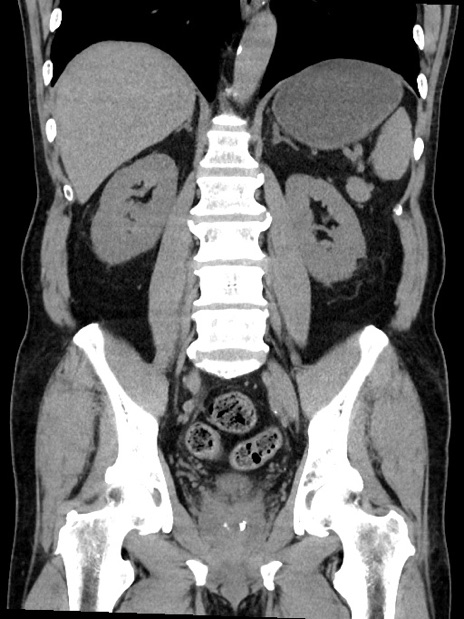

症例35(冠状断像)

【症例】70歳代 男性

【主訴】腹部膨満、嘔吐

【現病歴】昨日より腹部膨満感出現。本日増悪し、仙痛出現。嘔吐あり、受診。

【既往歴】糖尿病、胆摘後

【身体所見】BP 149/80mmHg、HR 74/min、BT 35.9℃、腹部:膨満、軟、圧痛なし。腸雑音減弱あり。上腹部正中切開瘢痕あり。

【データ】WBC 13500、CRP 1.72